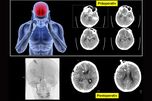

Die spontane intrazerebrale Blutung, meistens hochdruckbedingte Hirnblutung, liegt im Gehirn und resultiert in einer Beeinträchtigung der Hirnfunktion betroffener Hirnareale. Durch Größe und Lokalisation der Blutung wird deren raumforderndes Verhalten bestimmt.

Eine frühzeitige Ausräumung der Blutung durch minimal-invasive mikrochirurgische Ausräumung vermeidet sekundäre Komplikationen. Der noch nicht fest geronnene Koagel kann in diesem Stadium mit dem Sauger ohne bedeutendes zusätzliches chirurgisches Trauma entfernt werden. Die Absaugung des Hämatoms kann mit Hilfe ein Neuronavigationsgerätes durchgeführt werden.

Weitere Möglichkeiten der operativen Behandlung in unserer Klinik sind die Stereotaktische Lyse durch zielgerichte implantierte Katheter und die Endoskopische Absaugung.

Die folgende Animation zeigt: eine Intracerebrale Blutung im Stammgaglienbereich. CT- Ergebnisse nach akuter mikrochirurgischer Entlastung der Blutungen (heller Bezirk). Das Video zeigt die Mikrochirurgische Absaugung oben prä- und unten postoperativ.